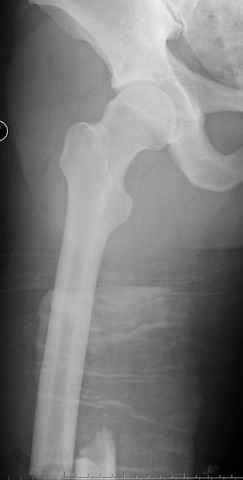

03.14.2005

больному 42, автоавария, политравма, открытая черепномозговая травма, безсознании, открытый перелом бедра, размозжение мягких тканей, дефект кожи на передней поверхности бедра около 13 см2 от ожога, компартмент синдром.

По поводу открытого перелома больной ургентно взят на ретроградное интрамедулярное штифтование, после рутинного дебрайдмента и фасциотомии на бедре и на голени.

перелом бедра